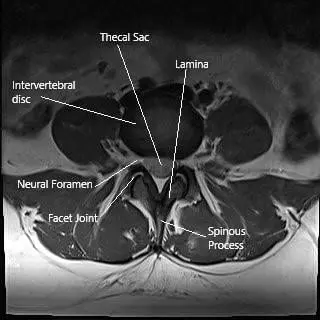

MRI image showing the axial section of the lumbar spine.